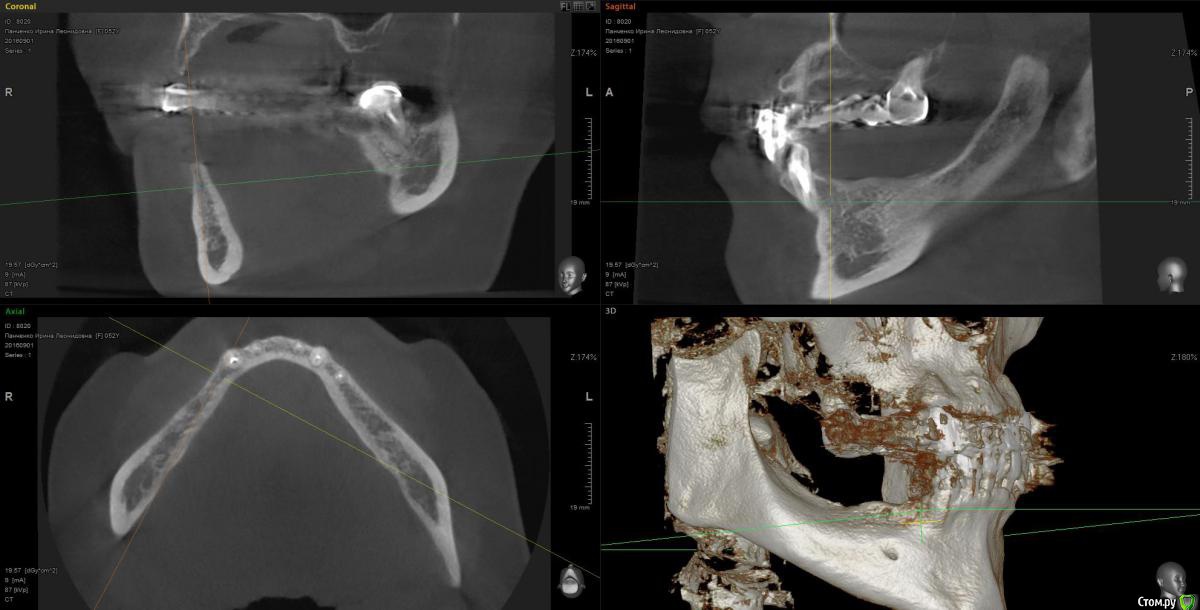

Kostoprav Опубликовано 13 марта, 2017 Поделиться Опубликовано 13 марта, 2017 рецепт сосиски: 70%биопласт by владмива +30%аутокость, мембрана hyprosorb кт до кт сразу после имплантации кт через пол года 3 Ссылка на комментарий

Kostoprav Опубликовано 14 марта, 2017 Автор Поделиться Опубликовано 14 марта, 2017 по порядку 8 Ссылка на комментарий